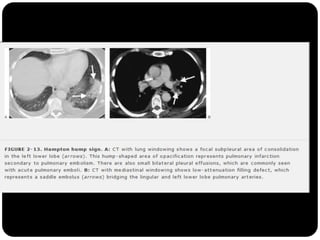

Sinal de Westermark

Sinal da corcova de Hampton